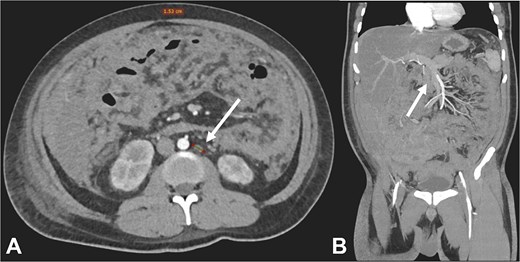

Postoperatively, suspected PTB was evaluated. Diagnostic tests, including sputum smear microscopy and GeneXpert MTB/RIF, peritoneal fluid culture and microscopy, and auramine-rhodamine stool staining, were negative. Thoracoabdominal CT (Figs 2 and 3) revealed generalized PC, plaque-like involvement at the hepatic flexure of the colon, and inflammatory lymph nodes. Histopathology provided the definitive diagnosis of NHL (Figs 4 and 5). Following an uneventful postoperative recovery, the patient was discharged after one week and referred to a tertiary care center, where chemotherapy was initiated, leading to significant improvement.

Contrast-enhanced CT in the arterial phase: Axial view (A) and coronal reconstruction (B) demonstrated mesenteric lymphadenopathy measuring up to 1.53 cm (white arrows).